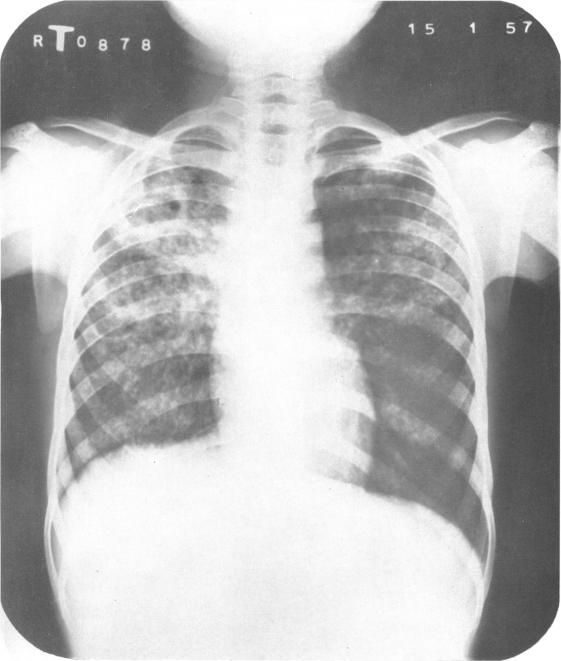

In India, as in most under-development countries, the tuberculosis problem is aggravated by an acute shortage of sanatorium beds. The number of active cases of tuberculosis in the country has been estimated at 2 (1/2) million, but only 23 000 tuberculosis beds are available. In these circumstances great importance attaches to the possibility of applying mass domiciliary chemotherapy as a substitute for sanatorium treatment in cases of pulmonary tuberculosis. The findings of the present study, based on a comparison of the two types of treatment over a period of 12 months, show that despite the manifest advantages of sanatorium care-rest, adequate diet, nursing and supervised medicine-taking-the merits of domiciliary chemotherapy are comparable to those of sanatorium treatment, and that it would therefore be appropriate to treat the majority of patients at home, provided an adequate service were established.